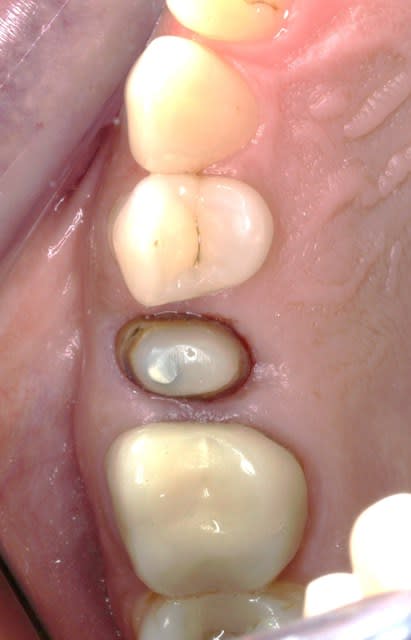

encore un petit cas .

je n ai pas de radio de départ .

ccm sur ic , ancienne , ic a clavette qui faisait clic cloc depuis un moment ." ça bouge mais ça tient bien " .

Arrache couronne façon HODINA pour faire sauter l ic coincé par la clavette . ca pue ç est mou et voila que ça pisse du fond,et meme du palais par une carie infra osseuse.

j essaie de netoyer les canaux et la je la creve pour de bon !

Remplissage au lentulo pate comme on ferait le plein de la vespa histoire de se détendre + .rdv pour extraction.

Alors là si il y en a un qui me dit que ç est pas un cas exteme,il faudra qu'il m explique sur qui il fait des implants ou des bridges.

ci joint la radio le jour du sc33 +taille, 3 semaines apres et sans contention.